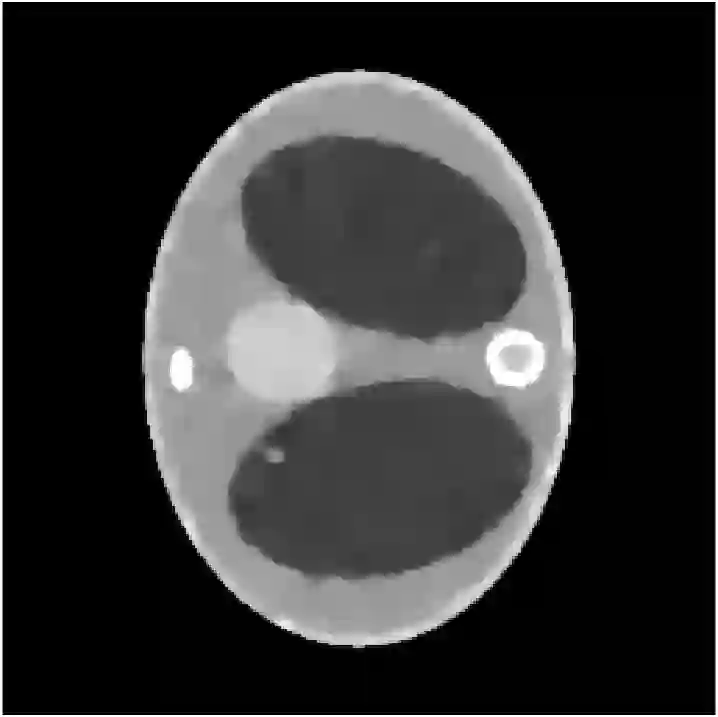

The recent development of energy-resolving scintillation crystals opens the way to new types of applications and imaging systems. In the context of computerized tomography (CT), it enables to use the energy as a dimension of information supplementing the source and detector positions. It is then crucial to relate the energy measurements to the properties of Compton scattering, the dominant interaction between photons and matter. An appropriate model of the spectral data leads to the concept of Compton scattering tomography (CST). Multiple-order scattering constitutes the major difficulty of CST. It is, in general, impossible to know how many times a photon was scattered before being measured. In the literature, this nature of the spectral data has often been eluded by considering only the first-order scattering in models of the spectral data. This consideration, however, does not represent the reality as second- and higher-order scattering are a substantial part of the spectral measurement. In this work, we propose to tackle this difficulty by an analysis of the spectral data in terms of modeling and mapping properties. Due to the complexity of the multiple order scattering, we model and study the second-order scattering and extend the results to the higher orders by conjecture. The study ends up with a general reconstruction strategy based on the variations of the spectral data which is illustrated by simulations on a joint CST-CT fan beam scanner. We further show how the method can be extended to high energetic polychromatic radiation sources.